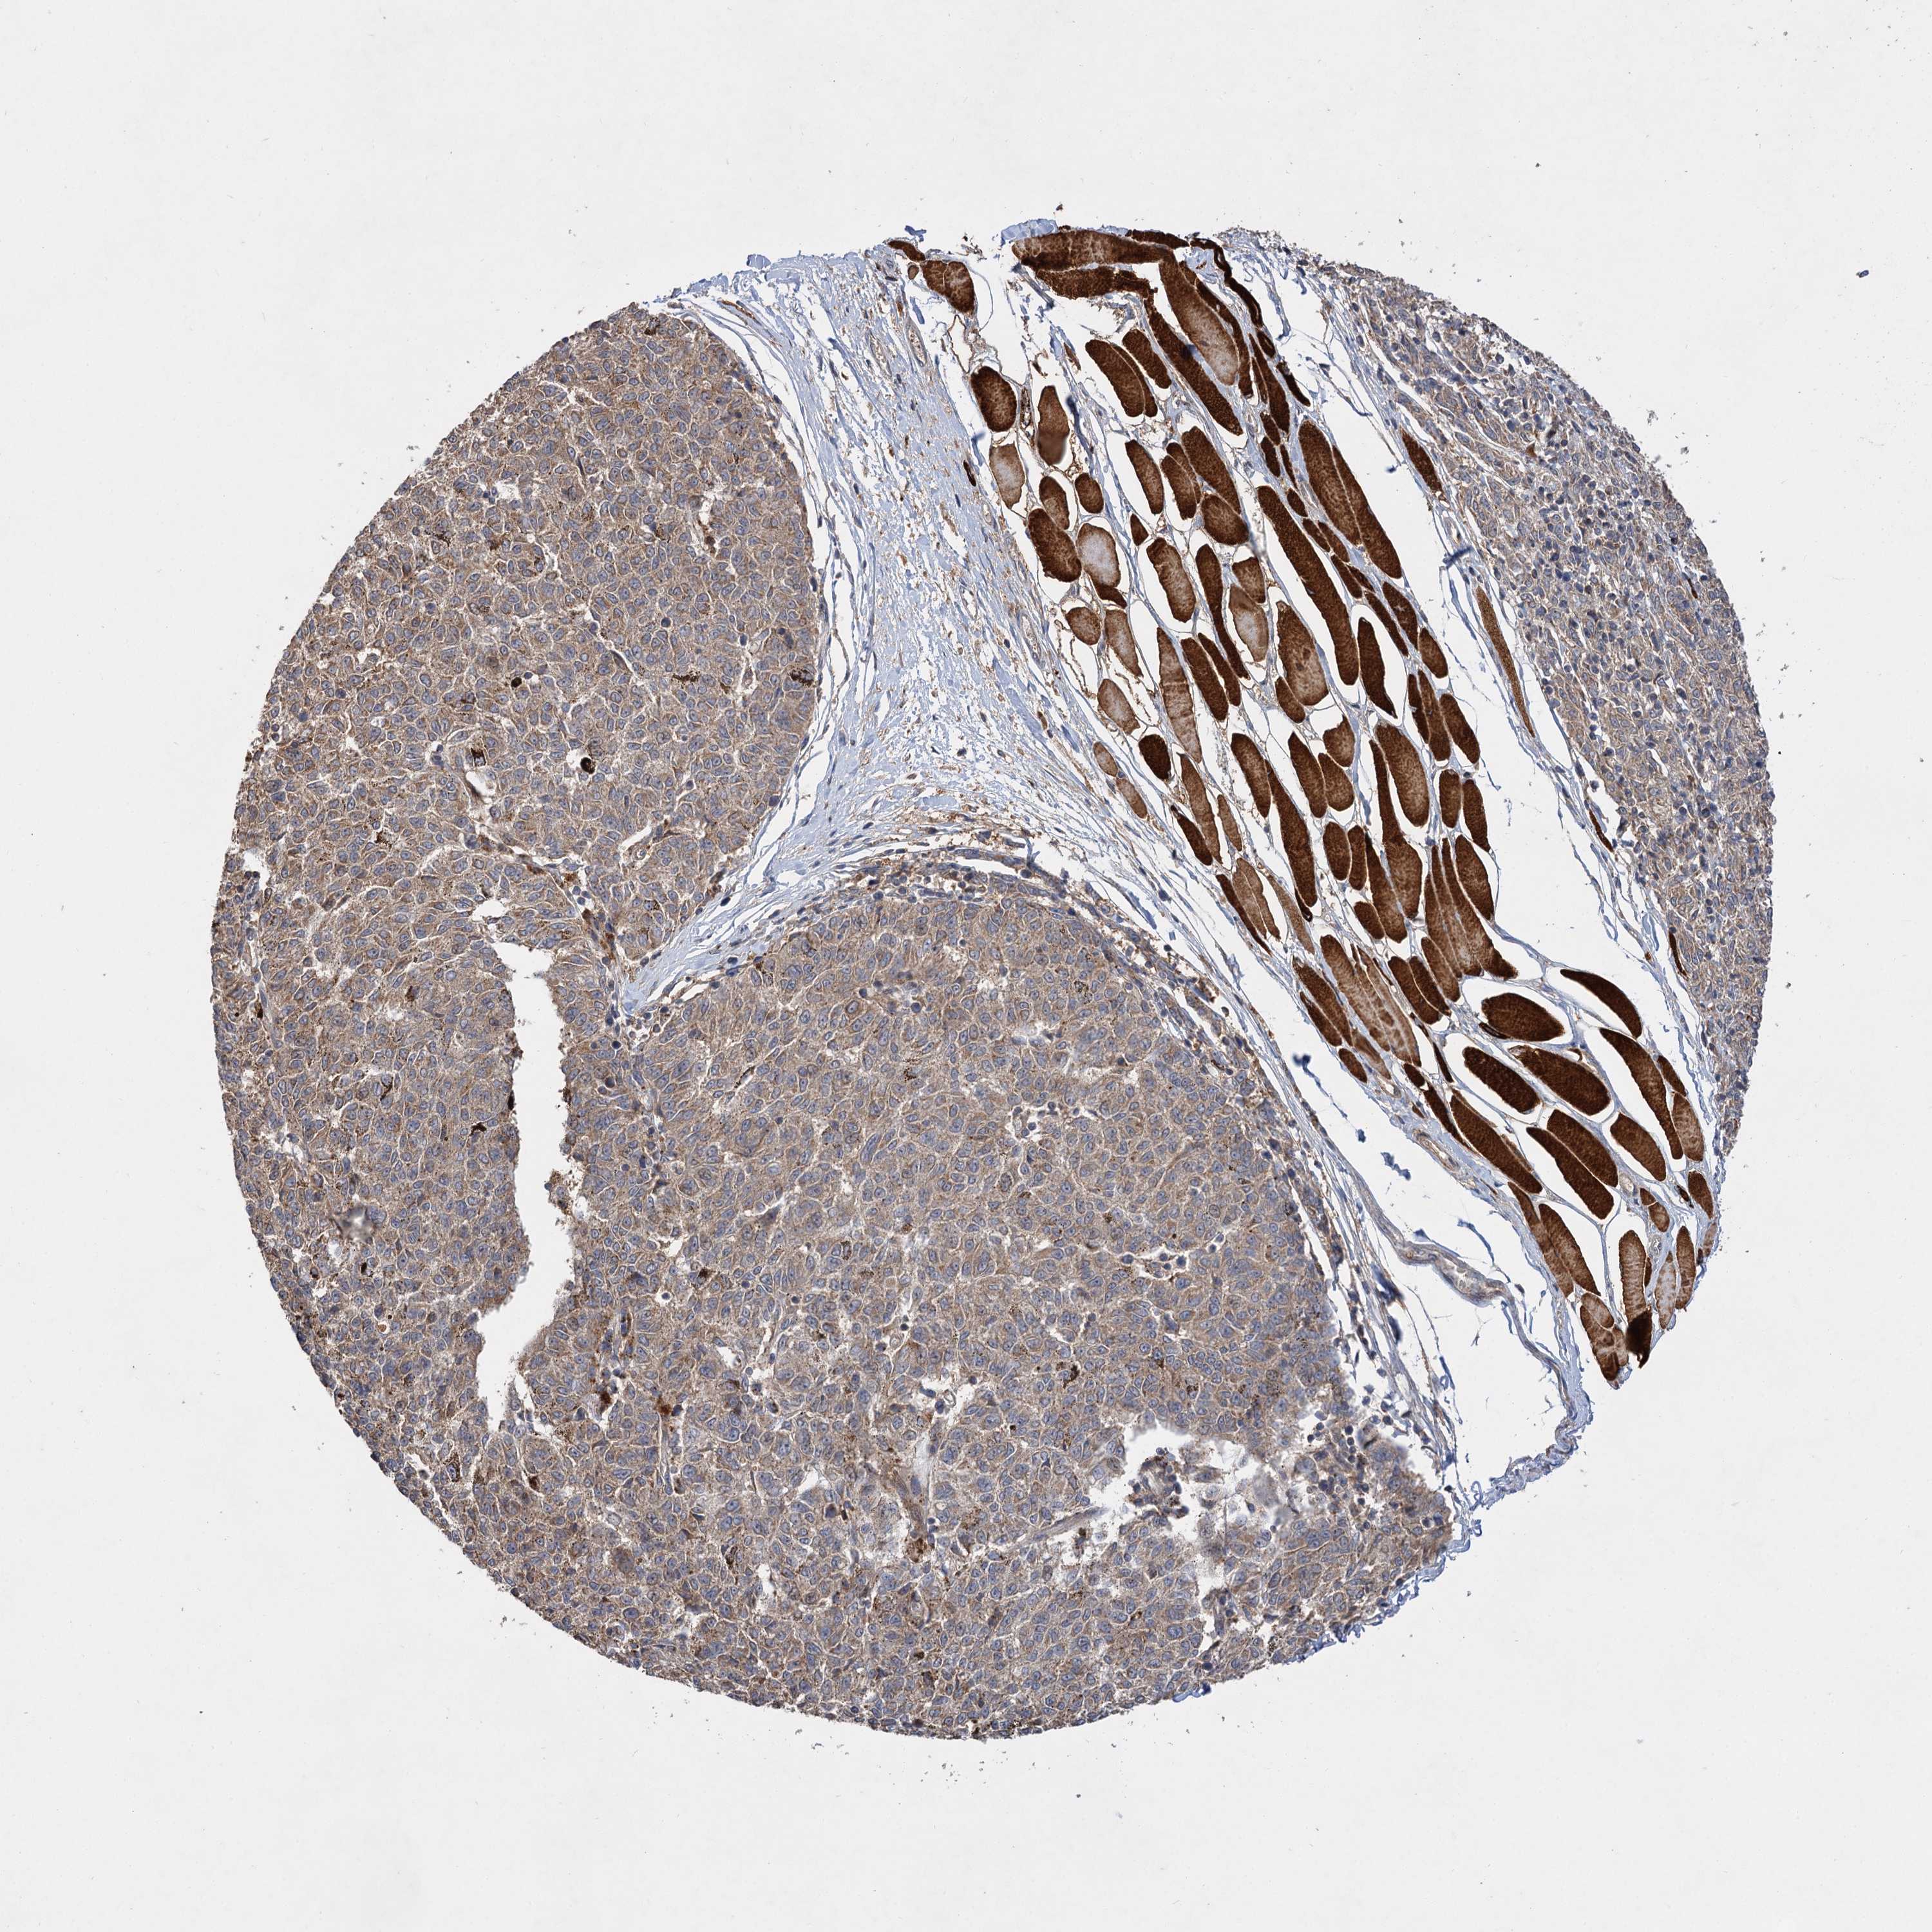

MELANOMA - Protein expressioni

A mouse-over function shows sample information and annotation data. Click on an image to view it in a full screen mode. Samples can be filtered based on level of antibody staining by selecting one or several of the following categories: high, medium, low and not detected. The assay and annotation is described here.

Note that samples used for immunohistochemistry by the Human Protein Atlas do not correspond to samples in the TCGA dataset.

Antibody stainingi

Antibody staining in the annotated cell types in the current human tissue is reported as not detected, low, medium, or high, based on conventional immunohistochemistry profiling in selected tissues. This score is based on the combination of the staining intensity and fraction of stained cells.

Each image is clickable and will lead to virtual microscopy that enables deeper exploration of all samples and also displays staining intensity scores, fraction scores and subcellular localization as well as patient and tissue information for each sample.

Antibody HPA038850

Antibody HPA038851

Staining

High

Medium

Low

Not detected

Intensity

Strong

Moderate

Weak

Negative

Quantity

>75%

75%-25%

<25%

None

Location

Nuclear

Cytoplasmic/membranous

Cytoplasmic/membranous,nuclear

Malignant melanoma, NOS

Malignant melanoma, Metastatic site